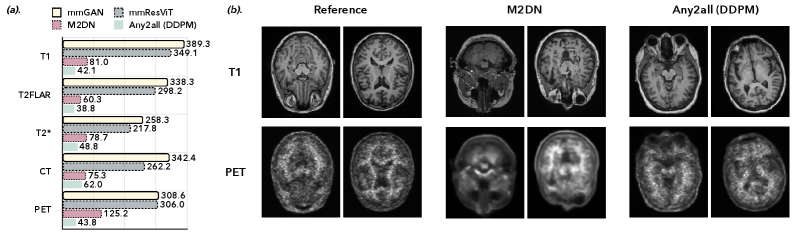

Refer to caption

Figure 2: Qualitative and quantitative evaluation of unconditional image generation. (a): Quantitative evaluation shows that Any2all achieves superior perceptual quality, reflected by lower FID scores across all modalities compared to baseline methods. The Any2all results are generated using a standard DDPM sampler from a single, unconditionally trained model. (b): Qualitative comparison of T1 MRI and PET images generated by Any2all and M2DN (a baseline trained on mixed conditional/unconditional tasks). This figure shows that the images from Any2all exhibit finer anatomical details and fewer artifacts, visually confirming the superior quality suggested by the quantitative metrics.

Figure 2 compares the performance of Any2all, mmGAN, mmResViT, and M2DN in generating realistic multimodal images from pure noise. Figure 2a presents a quantitative evaluation (FID \downarrow) of the generated images across all modalities. The results show that Any2all achieves lower FID scores than all baselines across all target modalities, demonstrating the superior perceptual quality of its learned generative prior. Figure 2b provides a qualitative comparison of T1 MR and PET images generated by M2DN and Any2all. The proposed Any2all model generates highly realistic samples, exhibiting fine anatomical details and negligible artifacts. Notably, Any2all produces sharp and clean images, whereas the images from M2DN suffer from blurring artifacts, particularly in the PET results.